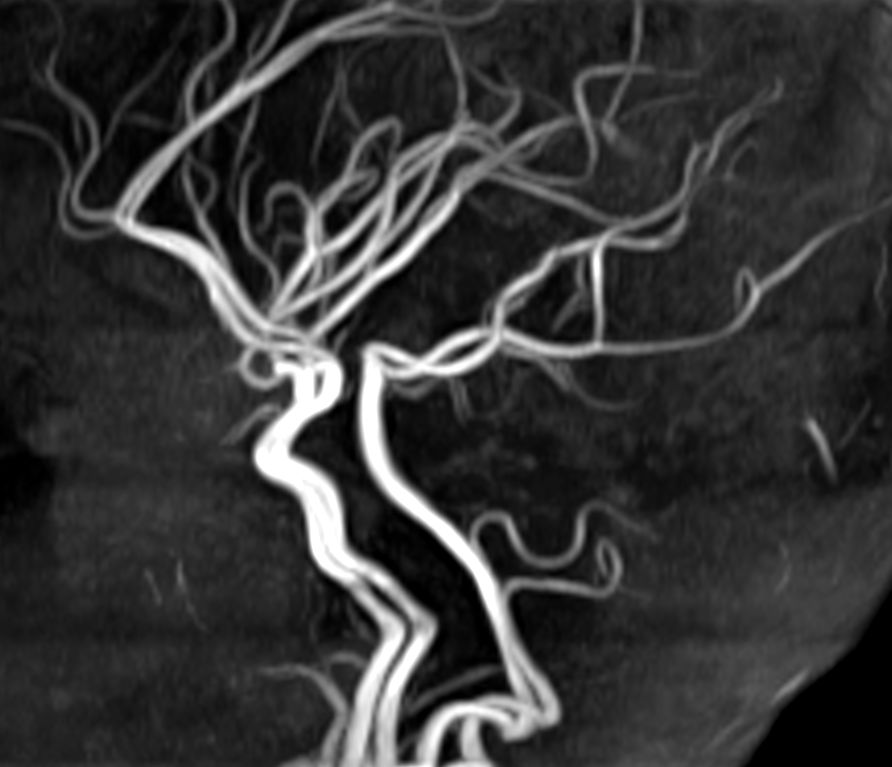

Coronal 3D TOF (MIP)